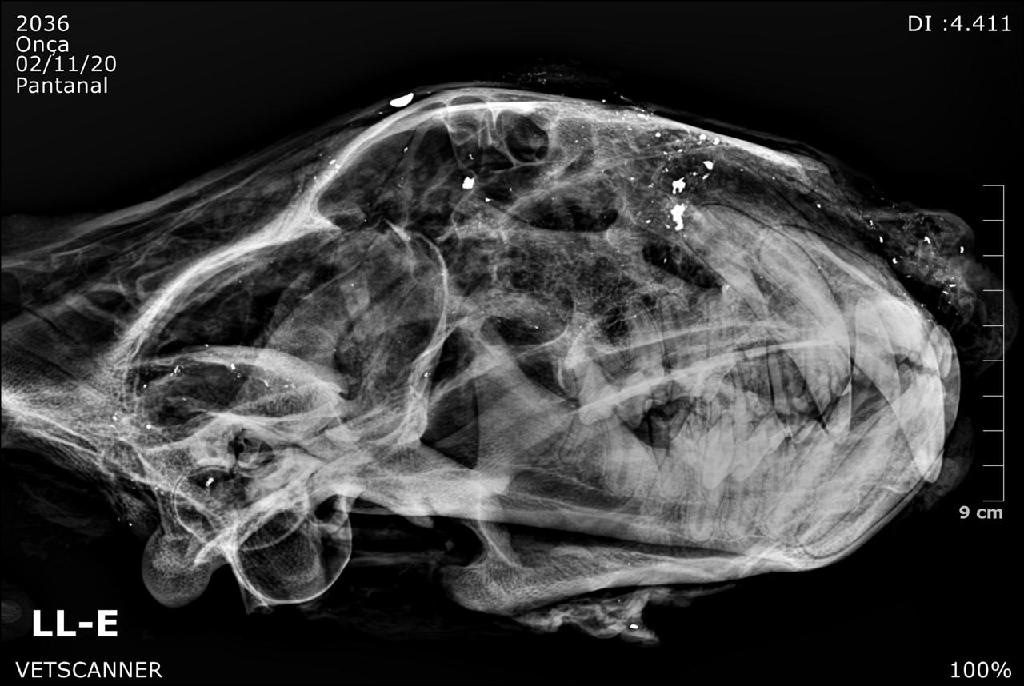

Imagem radiológica mostra bala estilhaçada em crânio de onça-pintada – Foto por: VetScanner

A cabeça do animal foi encontrada pendurada em uma árvore por uma equipe composta por agentes do Ibama e da Secretaria de Estado do Meio Ambiente que monitorava o bem-estar da fauna na região na região entre o Pixaim e o Porto Jofre, município de Poconé. As diligências ocorreram na última semana de outubro. As radiografias do crânio do animal mostraram a presença da bala estilhaçada, evidenciando o crime de caça.